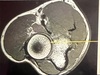

Q

Which arrow points to the laryngopharynx?

A

E